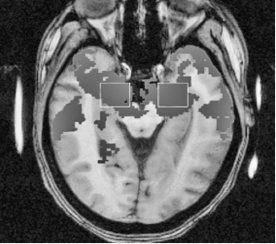

Полученные результаты послужили доказательством непревзойденной гениальности естественного отбора. Они показали значительное увеличение активности как миндалины (участка мозга, который играет ключевую роль в формировании эмоций), так и передней поясной коры (участка мозга, чувствительного к аномалиям). Это происходило в тот момент, когда на записи шли настоящие крики, в отличие от перекодированных фрагментов, и было более характерно для женщин, чем для мужчин. Такая реакция, по мнению Сандер, может отражать врожденную предрасположенность нервной системы женщины реагировать на звуки, издаваемые младенцами, до того как они научатся говорить (см. рис. 2.1 ниже).

Рис. 2.1a. Приблизительная картина областей активности мозга женщины, когда она слышит крик взрослого человека

Рис. 2.1b. Приблизительная картина областей активности мозга женщины, когда она слышит крик младенца

Рис. 2.1c. Приблизительная картина областей активности мозга мужчины, когда он слышит крик младенца

А когда Сандер сравнила активность миндалевидного тела испытуемых в тот момент, когда они слышат крик взрослого и крик ребенка, она испытала настоящее потрясение. Во втором случае активность мозга была в девять раз выше. Крик младенца, вопреки первому впечатлению, далеко не так прост, как кажется.